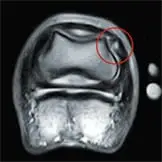

Die MRT-Untersuchung ermöglicht eine besonders detaillierte Darstellung von Weichteilstrukturen und Knochen, insbesondere im Bereich der Gliedmaßen. Besonders wertvoll ist sie für die Diagnostik im Hufbereich, da dort wichtige Strukturen wie die tiefe Beugesehne oder Schleimbeutel liegen, die mit anderen bildgebenden Verfahren nur schwer darstellbar sind.

Außerdem können Veränderungen im Knochenmark – sogenannte Knochenödeme – sichtbar gemacht werden. Diese Flüssigkeitsansammlungen im Knochen entstehen zum Beispiel bei Überlastung, Mikrofrakturen oder Entzündungen. Werden sie rechtzeitig erkannt, kann die Therapie gezielt angepasst werden, um schwerwiegendere Schäden wie Stressfrakturen oder chronische Lahmheiten zu vermeiden.